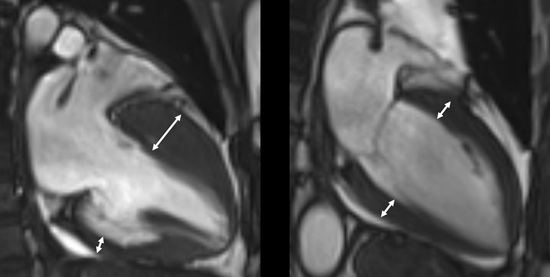

¡ã (¿ÞÂʺÎÅÍ) ºñÈļº ½É±Ùº´ÁõÀ» °¡Áø ȯÀÚÀÇ ÀÚ±â°ø¸í¿µ»ó, Á¤»ó ½ÉÀå ÀÚ±â°ø¸í¿µ»ó. °í·Á´ëÇб³ ¾È»êº´¿ø Á¦°ø

Áø´ÜÀº ½ÉÀåÃÊÀ½ÆÄ, ÀÚ±â°ø¸í¿µ»ó(MRI) µî ¿µ»ó°Ë»ç¸¦ ÅëÇØ ÀÌ·ïÁö¸ç, ºñÈÄµÈ ½É±Ù ³»¿¡ ¼¶À¯È­°¡ ÁøÇàµÅ Àְųª ±ÙÀ°Á¶Á÷ÀÌ Áö¹æÁ¶Á÷À¸·Î º¯¼ºÀÌ µÅ ÀÖ´Â »óŰ¡ °üÂûµÈ´Ù. ÇÏÁö¸¸ ÀÌ °°Àº Á¶Á÷º¯¼ºÀÌ ¾ø´Â ºñÈļº ½É±Ùº´Áõµµ ÀÖ´Â ¸¸Å­ Àü¹®ÀÇÀÇ Á¾ÇÕÀû ÆÇ´ÜÀÌ Áß¿äÇÏ´Ù.